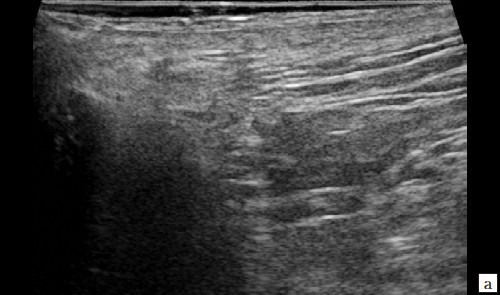

Рис. 1. а, б – В-режим. В перианальной области слева на глубине 0,6 см от поверхности кожи определяется гипоэхогенное жидкостное образование с четкими неровными контурами с наличием неоднородного гиперэхогенного подвижного содержимого размером 3,9×2,1×1,9 см, объемом 8,24 мл с утолщенными до 0,3 см стенками. Описываемое образование прилежит к передне-боковой утолщенной до 1,0 см стенке анального канала, нечетко от нее дифференцируется (стрелки);

Рис. 2. а, б – В-режим. Через 3 дня после оперативного вмешательства. Описываемое гипоэхогенное жидкостное образование с четкими неровными контурами с наличием неоднородного гиперэхогенного подвижного содержимого уменьшилось в размере до 2,4×1,7×1,8 см, до объема 3,84 мл (стрелки);

Рис. 3. а, б – В-режим. Через 14 дней после оперативного вмешательства. Гипоэхогенное жидкостное образование с четкими неровными контурами в перианальной области уменьшилось в размерах до 1,1×0,6×0,8 см, объемом 0,29 мл (стрелки);